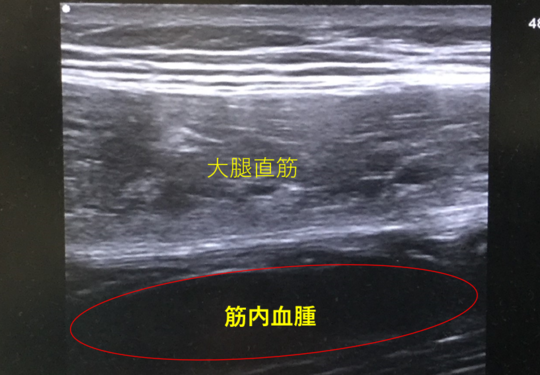

中学3年生・男子:バスケットボールで相手の膝が大腿部前面に入り受傷したものです。

いわゆる打撲の中にはエコー画像のように筋肉内に血腫(赤〇部分)がみられるものが時々見られます。

このような血腫がある場合は膝関節の可動域制限(膝が曲がらない)が強く起こり、エコーでよく観察できます。

治療としてはギプス固定を行う場合と、医科にて穿刺する場合があります。

この血腫がある状態で無理に運動を続けていると骨化性筋炎と言って筋肉の一部が骨化してしまいます。骨化性筋炎が起こると治療に非常に長い時間がかかるため注意が必要です。

エコー画像(筋内に巨大血腫がみられる)